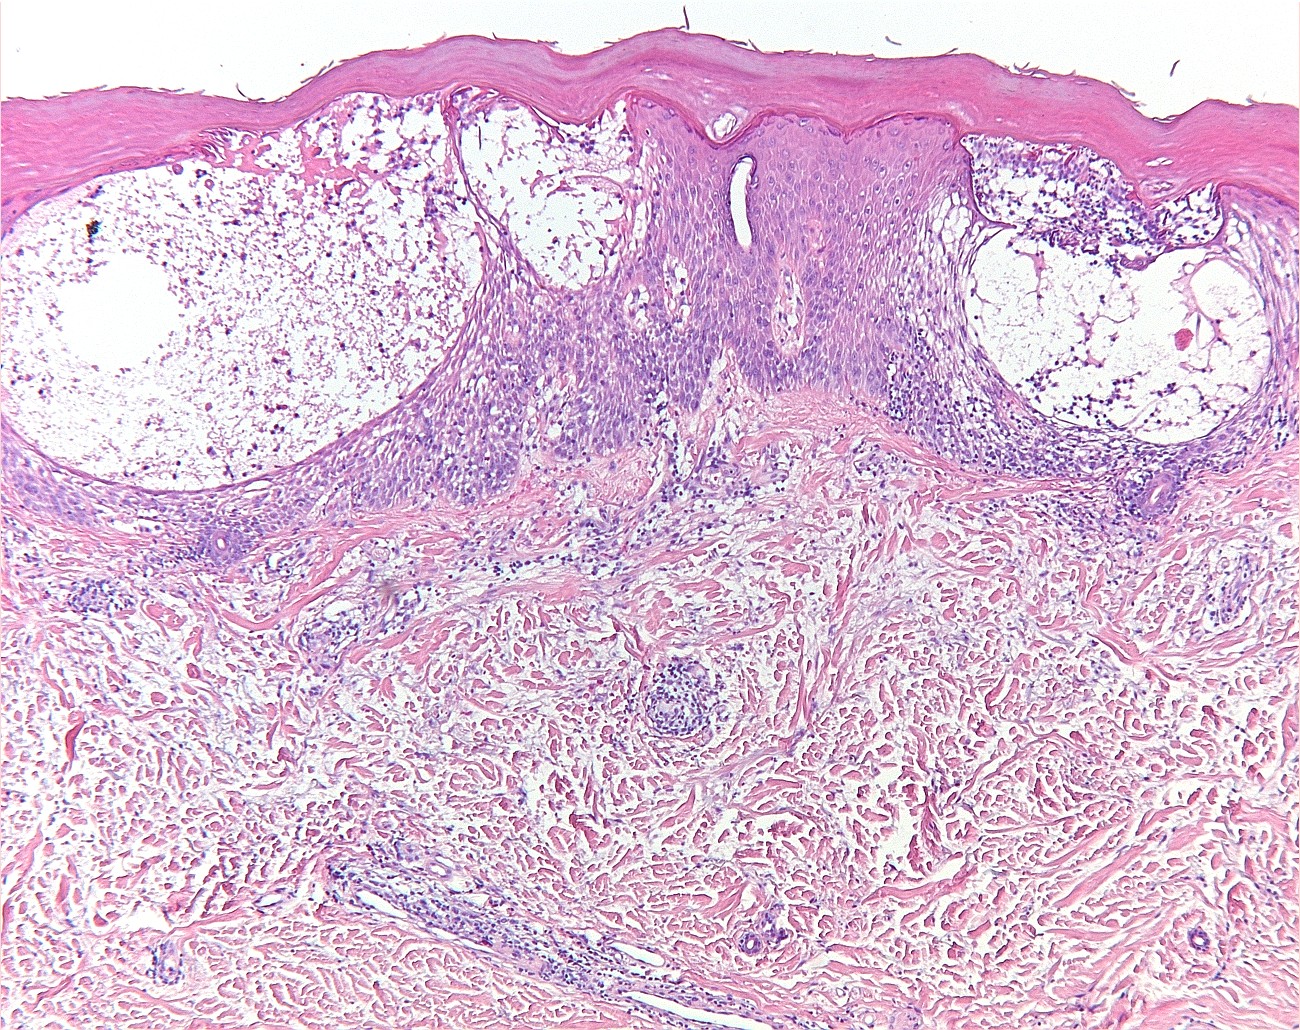

Klinisch beeld:Kleine tot grote spongiotische

vesikels tot bullae, vooral op laterale zijden vingers beide handen, handpalmen

en voetzolen (zelden). Het kan acuut zijn, recidiverend, of chronisch. Gaat

gepaard met jeuk of branderigheid. Bij warm weer is het erger. Soms treedt secundaire

infectie op met als mogelijk complicatie erysipelas of lymfangitis. Bij chronische

varianten kan ook nageldystrofie optreden.

PA:

het histologisch beeld in de fase dat er klinisch vesikels zijn is dat van een

acuut eczeem met spongiose.